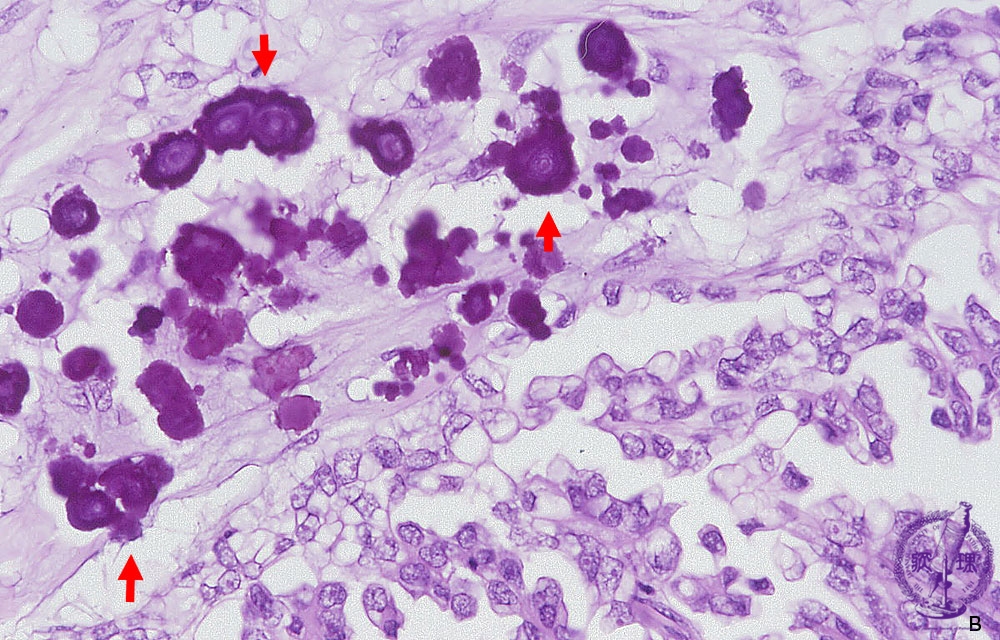

内膜症性嚢胞で壁在結節をみたときの鑑別診断

6. チョコレート嚢胞に隆起性病変を認めたときに、癌・非癌を区別するにはどうすればいいのか? 日本産婦人科医会